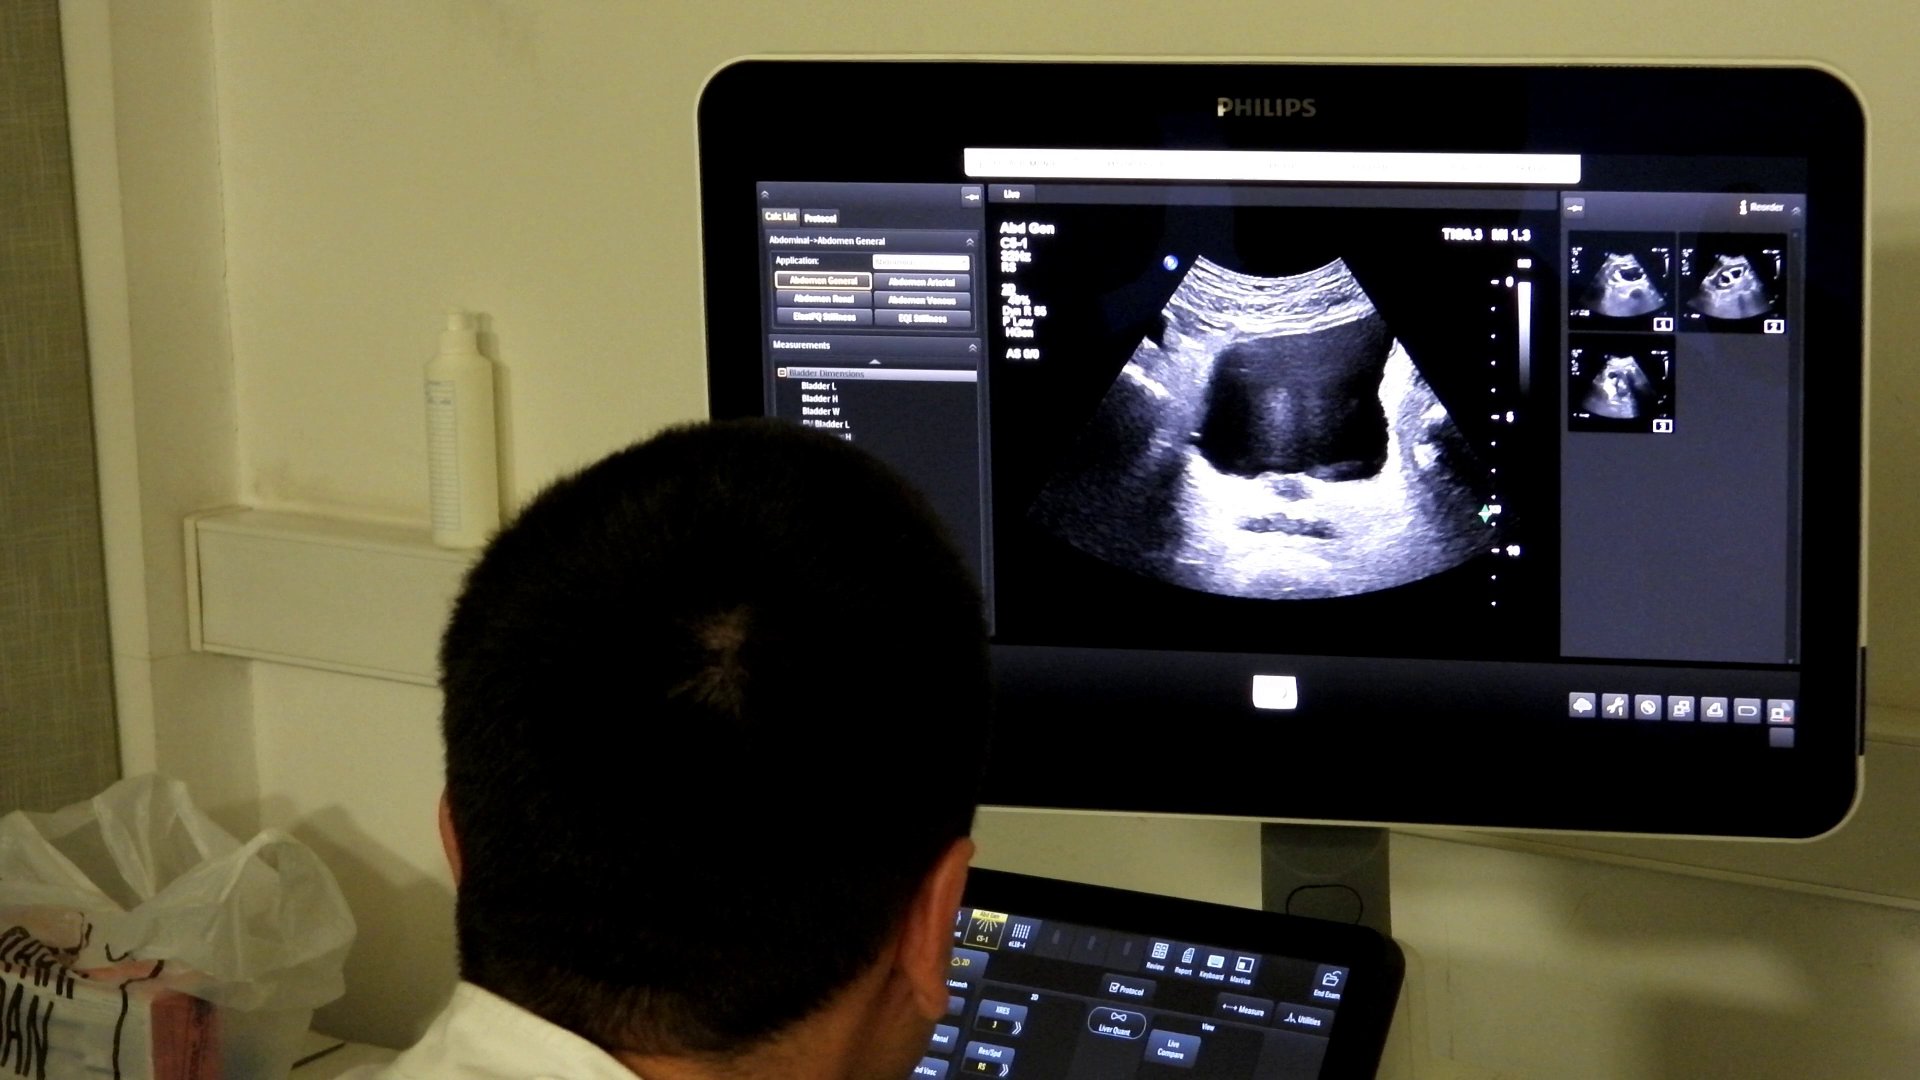

Dr. spec. radiolog Aida Vehabović iz Kantonalne bolnice Zenica (KBZ) je pojasnila je strukturu edukacije i značaj praktičnog rada.

– Prvi napredni kurs Ultrazvučne škole abdomena, je dio kontinuirane edukacije koja se sastoji od bazičnog i naprednog kursa. Devet ljekara steklo je certifikate za samostalni rad u ultrazvučnoj dijagnostici abdomena. Dio vizije kontinuirane edukacije jeste jačanje zdravstvenog sistema u smislu dostupnosti ove dijagnostičke metode pacijentima u njihovim lokalnim zdravstvenim ustanovama, rekla je dr. Vehabović.

Ona je naglasila da su certifikate dobili mladi ljekari koji će se baviti samostalnim radom u ovoj oblasti.

– Polaznici su tokom kursa imali priliku raditi sa velikim brojem pacijenata različitih kliničkih stanja i patologija, uključujući i rijetke, te su stekli stručnu kompetenciju za samostalan rad na što smo posebno ponosni, rekla je dr. Vehabović.